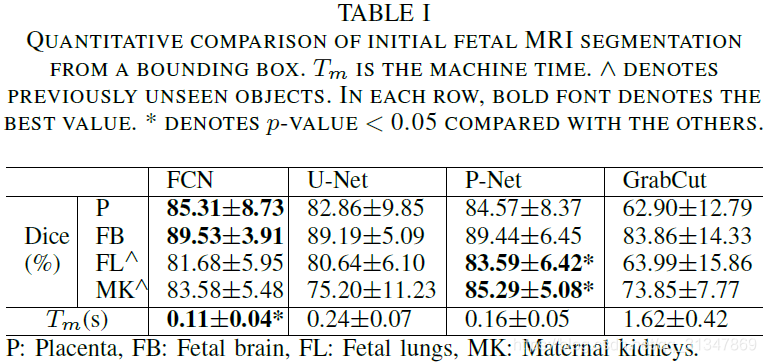

给出同样的 bounding box,作者将 P-Net 和之前的 FCN、U-Net 进行比较(2D分割),将 PC-Net 和 DeepMedic、HighRes3DNet 进行比较(3D分割)。

(1)对比 GrabCut,FCN,U-Net 和本文提出的 P-Net 的初始分割结果:

GrabCut 只有在对比度比较大的脑部图像上分割效果比较好

对于训练过的特定目标:Placenta 和 Fetal brain,FCN、U-Net 和 P-Net 取得的分割效果差不多,都很接近 ground truth

但是对于未见目标:Fetal lungs 和 Maternal kidneys,P-Net 的分割结果明显比 FCN 和 U-Net 好很多

具体比较如下:从表中可以看出 P-Net 虽然在 Placenta 和 Fetal brain 上的分割效果不比 FCN,但是对于未见目标的分割效果是最好的。